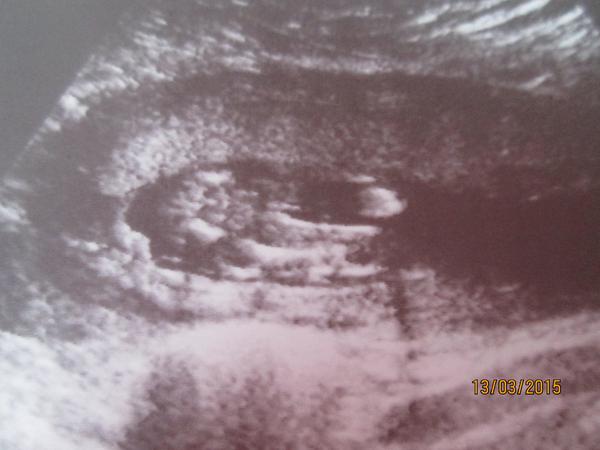

Ahoj holky.Dnes kontrola u dr. jsem 16 tt.Vyfotila mi rozkrok,ale já se v tom nevyzdám.Nevím ani kde jsou nohy natož kde má být údajně pohlaví.Je tu nějaký odborník který to pozná? 🙂 Dr. mě napíná a prý nechá na jiném dr. ať mi řekne co to bude.Kontrola ale až za měsíc 😒

@jarmulka Nevyznáš se v tom prosím ty? 😒 Obě fotky jsou stejné,jen ta druhá je zvětšenina

A můžete mi prosím holky některá z vás nějak zakroužkovat,kde mám hledat?Já fakt ani nemám ponětí 😀

Holky,kde tam vidite pindoura s kulkama?ja se tady snazim stahnout aplikaci do telefonu,abych mohla fotku oznacit a furt nemuzu nic najit ☹ chtela bych oznacit to kavove zrno,ktere vidim 😀

@anetka1701 no tak tam presne vidim kavove zrno 😀

Akorat jsem na telefonu a nemuzu to zakrouzkovat,nemuzu najit aplikaci,abych mohla kreslit do fotky 😁

@emily2015 kávová zrna jsem viděla zatím naživo dvě a nějak to vypadalo prostě jinak než tohle... :oD

@anetka1701 ja jsem zase videla na utz pytlik s kulkama a take to vypada naprosto jinak 😀